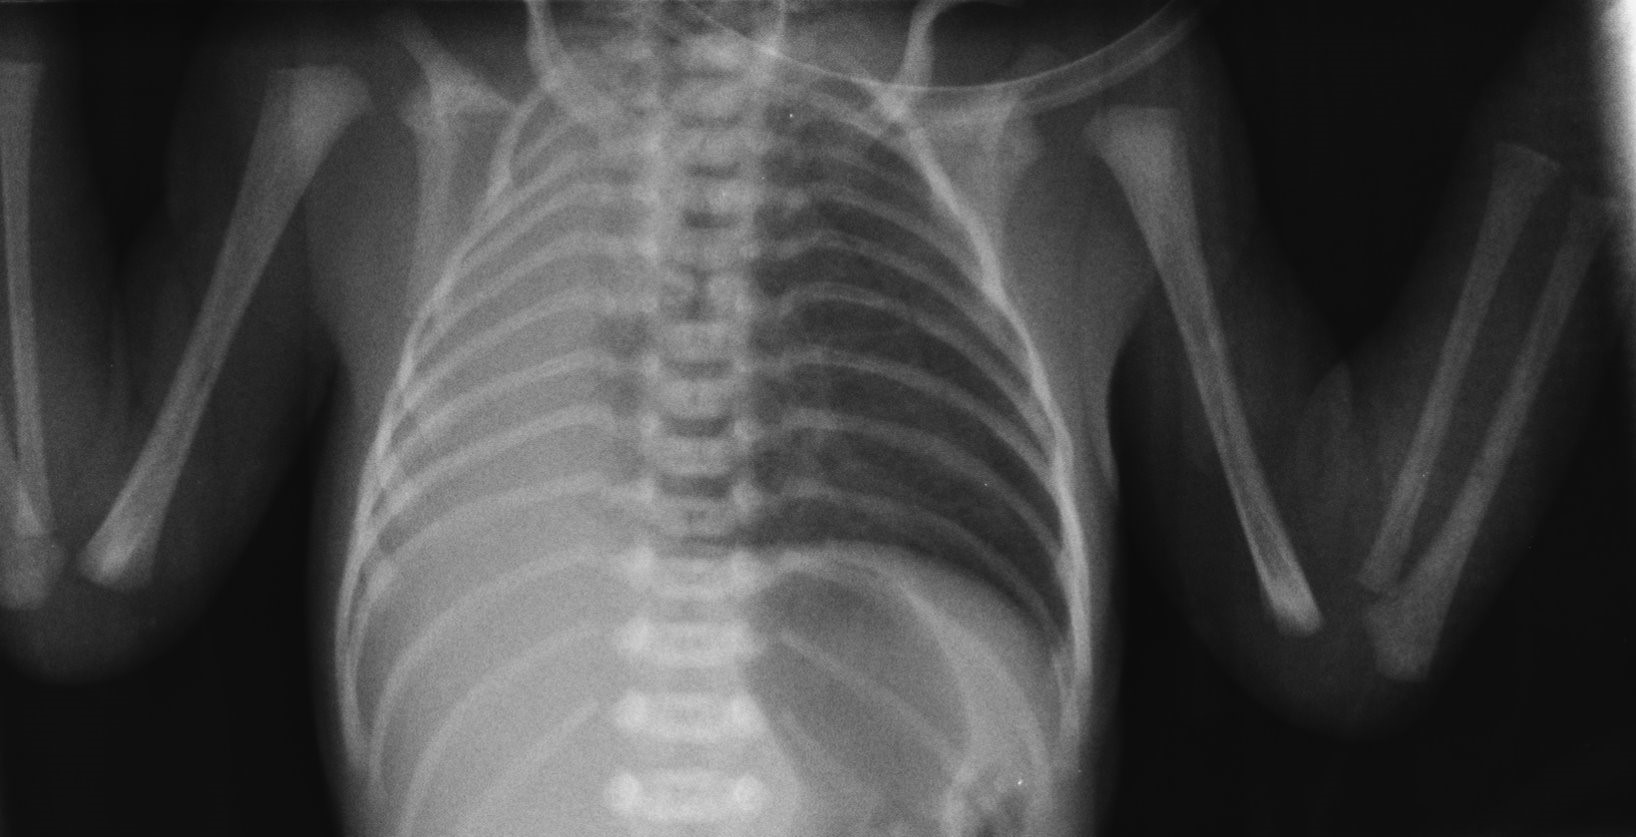

Recién nacido de 33 semanas y 1500 g de peso que ingresa por prematuridad y distrés respiratorio. Embarazo controlado irregularmente. Apgar 6/8. En la exploración al nacimiento se detecta tiraje sub- e intercostal leve, hipoventilación en hemitórax derecho, tonos cardiacos desplazados ipsilateralmente y abdomen excavado. Precisa ventilación no invasiva con presión positiva continua de la vía aérea (CPAP) durante las primeras horas de vida, quedando posteriormente en respiración espontánea. Se realiza una radiografía de tórax (Figura 1).